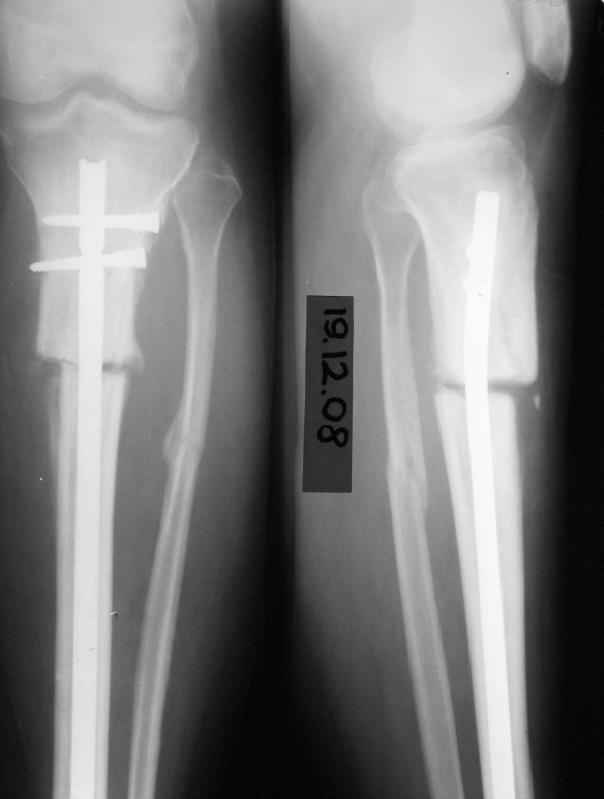

История следующая: женщина (медработник)сбита машиной 7.06.08 - о.перелом обоих костей голени в/3 со смещением. В ПДО ПХО раны,вытяжение за пяточную кость. После заживления раны 20.06.08 выполнен остеосинтез блокирующем стержнем. в течение первого месяца после травмы сохранялась субфебрильная температура на фоне приема антибиотиков. Затем температура стабилизировалась.Б-ая как положено ходила в гипсе на костылях. На контрольных рентгенограммах консолидация не достигалась, иммобилизация продлевалась. Пациентка на себе опробовала все препараты костной регенерации. В марте удален один из фиксирующих винтов. На сегодняшний день идет 11 мес. после травмы. Решается вопрос о инвалидности. Буду благодарен за предложения по дальнейшему ведению больной. Операция?

Сегодня мы имеем консолидированный перелом малоберцовой кости, являющийся распоркой и отстутствие консолидации большеберцовой кости, и ваша динамизация гвоздя, выполненная с опозданием не ришила проблем.

Судя по изменению положения гвоздя в послеоперационном периоде (хотя и в благоприятную сторону) нестабильность была очевидна. И не стоило

пытаться решить проблему гипсом, надо было сразу делать ревизионный остеосинтез. В итоге пациент бы не потерял год на лечение.

Судя по разнице послеоперационных и последующих снимков, с самого начала уже была задана "гипердинамизация", раз положение отломков изменялось буквально на сантиметры.